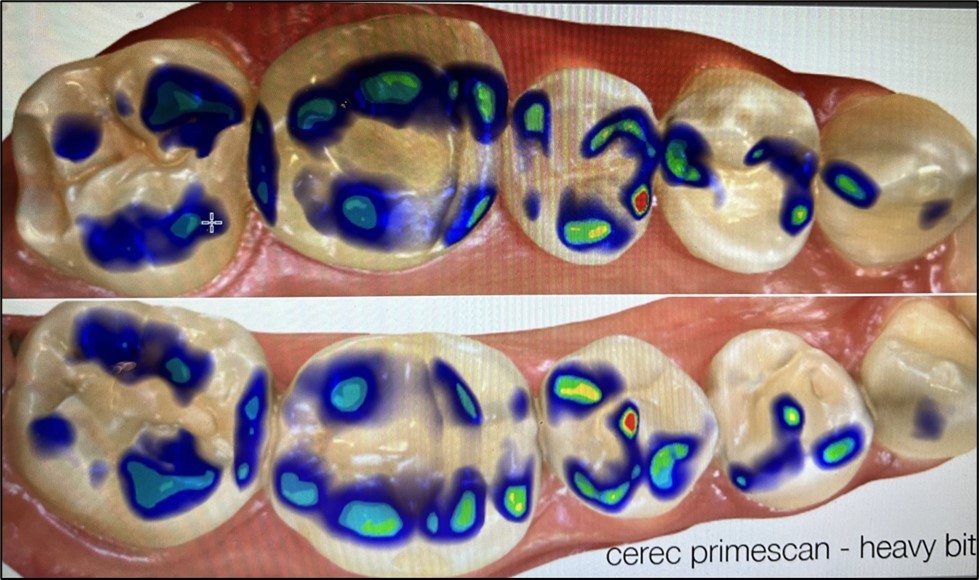

This observational study compares four clinically used methods for recording occlusal contacts. Recordings were made using each of four different methods on the same subject who volunteered participation. All recordings were made in office by one clinician (CS) during the same time period. A clinical subject with few restorations was selected and the subject agreed to the procedure along with the right to publish the results. There are no quantitative measurements. Ankylosis is a factor that was not addressed. The recording indicator systems evaluated were: 1. Accufilm (Parkell, Brentwood NY. USA). 2. Blue paper (Bausch, Nashua NH. USA), 3. Primescan (Densply/Serona, Waltham MA. USA), 4. PMscan (Mco, Boston MA. USA). In all procedures the subject was advised on how to close and the procedure was repeated. The subject made one hard closure into or onto the marking surface and the results were recorded and are displayed in (Figure 1) (Figure 2, Figure 3, Figure 4 )

Material 3: Primescan {Figure 3} recorded the occlusion digitally. Bites may vary because they are recorded digitally. Intensity of closure and parametric movements are not recorded.